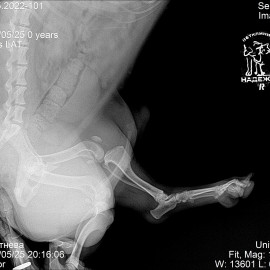

Наш пациент собака породы такса. Обратились в клинику с жалобами на отёк на правой задней лапе и потерю опороспособности. Были проведены исследования. Поставлен диагноз: перелом правого бедра. Проведена операция: остеосинтез правого бедра.

Снимок 2 после операции.